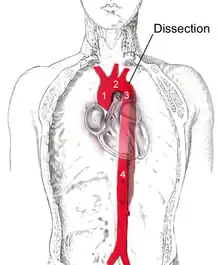

| Dissection of the descending part of the aorta (3), which starts from the left subclavian artery and extends to the abdominal aorta (4). The ascending aorta (1) and aortic arch (2) are not involved in this image. | |